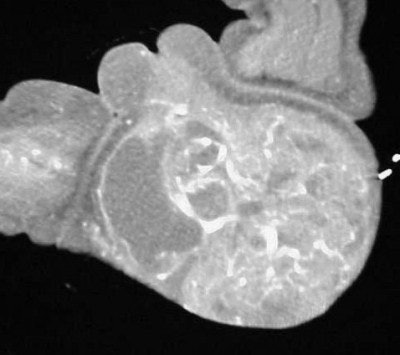

![]() |

| Figure TC 5 |

| Figure TC 6 |

The images (Figures TC 5 and TC 6) show, respectively, a sagittal and coronal MPR of the axial images, demonstrating the size and volume of the structure.